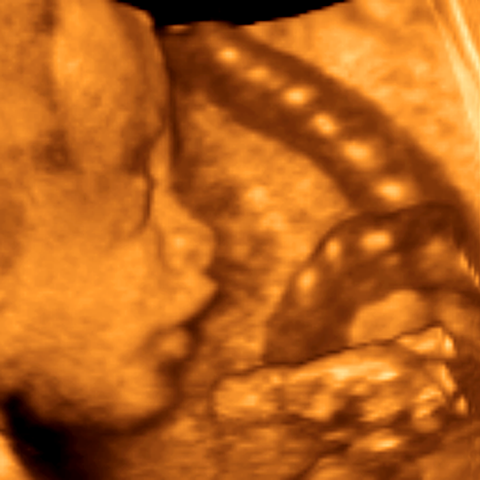

3rd trimester fetus